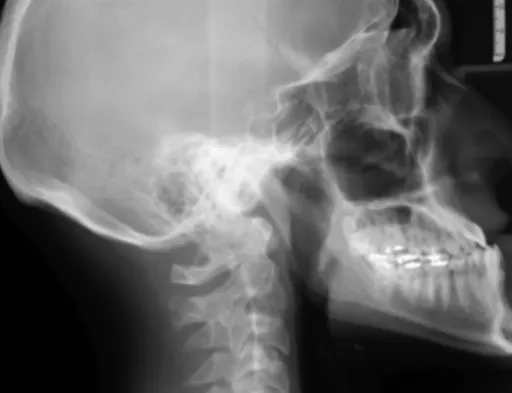

2.1. 허리 디스크 (추간판 탈출증)

가장 대표적인 신경 압박 원인 중 하나가 바로 허리 디스크, 즉 추간판 탈출증이에요. 허리 척추뼈 사이의 디스크(추간판)가 제자리에서 밀려나와 주변 신경을 누르는 거죠. ** 이때 신경이 눌리는 위치에 따라 엉덩이부터 다리까지 뻗치는 통증이나 저림, 감각 이상이 나타날 수 있어요. ** 허리도 아프고 다리도 저리다면, 의심해 볼 만해요.